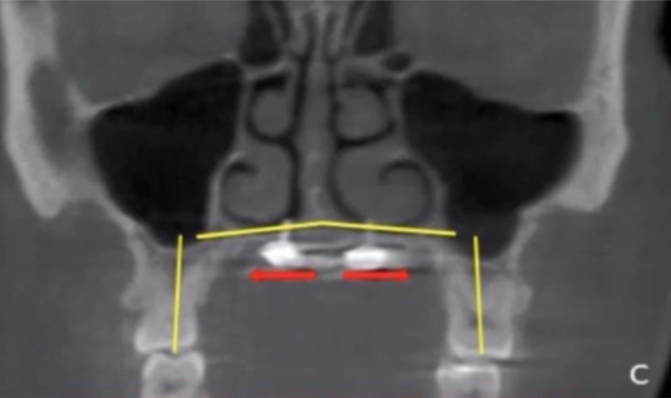

Red arrows in the bottom left X-ray above demarcate the amount of expansion. This X-ray is from three weeks after MARPE was placed. This area would normally be white, but instead it is dark!

The red lines in the bottom right picture above indicate the palatal suture, and the blue lines are the direction of the expansion. The palatal suture splits in the center of the palate and between the two front teeth. We just want to keep an eye on the two front teeth and make sure the bone is filling in before any movement is placed with Invisalign to close the space.